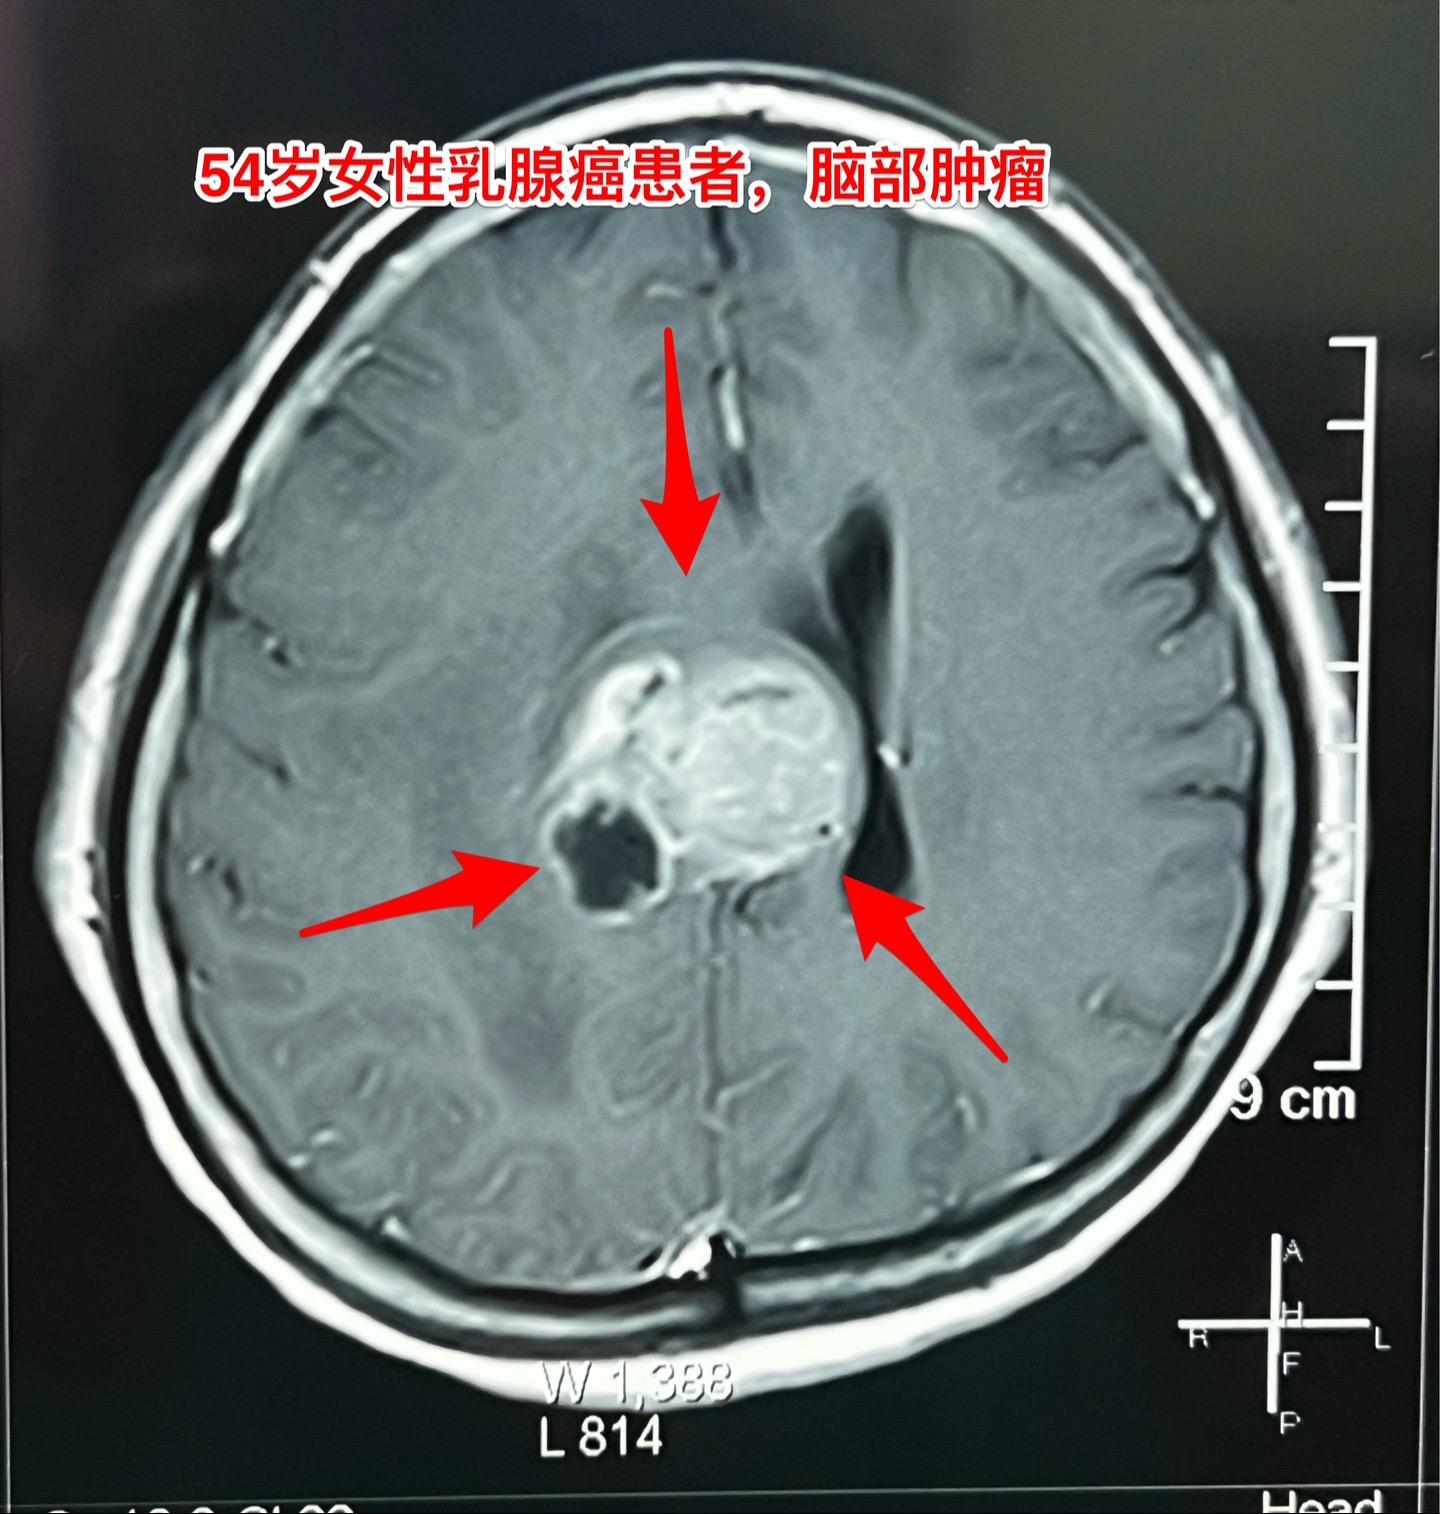

乳腺癌也能转移到脑部。脑部的转移瘤约80%来源于肺癌,绝大多数是腺癌。 乳腺癌发病率虽然低于肺癌,但也很常见。乳腺癌也可能转移到脑部。 这个54岁女性在7个月前先发现 脑部有个瘤,随后发现了乳腺癌,作了乳腺癌切除手术及内分泌治疗。多次复查磁共振显示脑部的瘤体积在增大,而且病人也出现头痛症状,故来作手术。 1月23日作了手术,顺利切除肿瘤。术前病人担忧出现偏瘫症状,手术后并没有出现。 针对这个病随后还需要综合治疗。